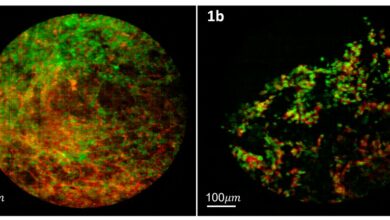

Construindo uma biópsia melhor com endomicroscopia confocal multiespectral

Exemplos de imagens pulmonares usando o instrumento MSCE e a combinação de corante proflavina rosa bengala. Nessas imagens, a proflavina…